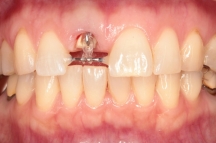

一番左写真は歯が折れてしまい、根っこだけの状態になってしまい、温存するために部分矯正中の写真です。

(表に仮歯をつけますので、見た目はおかしくない状態で過ごしていただきます)

MTM(部分矯正・Minor Tooth Movement)といって、

健全な根っこを部分矯正でひっぱり出すことで抜かずに温存する治療を行うことになりました。